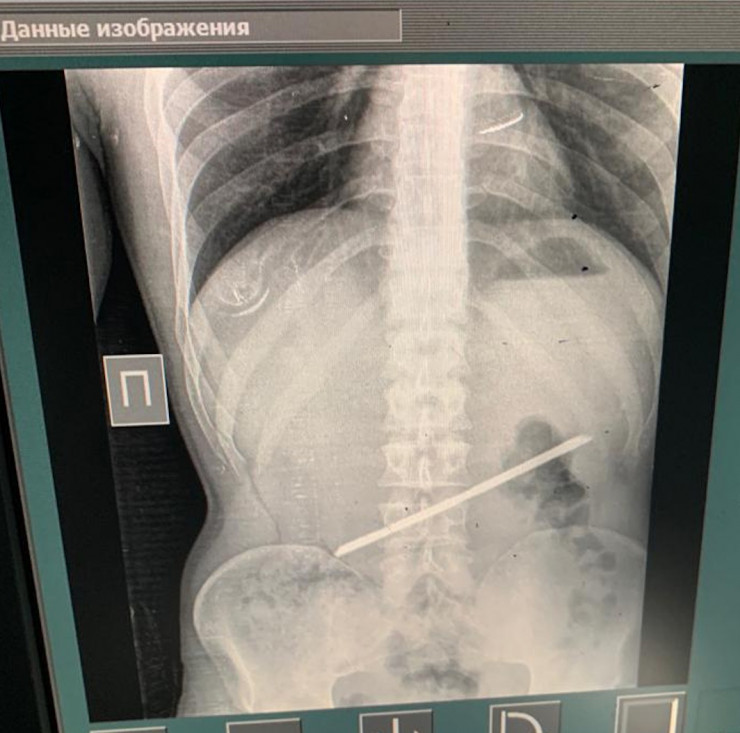

Алматинец 2,5 года прожил с 25-сантиметровой арматурой в желудке

Хирурги в Алматы извлекли 25-сантиметровую арматуру из желудка мужчины, передает Tengrinews.kz со ссылкой на пресс-службу Управления общественного здоровья Алматы.

С арматурой в желудке мужчина прожил 2,5 года и только сейчас обратился с проблемой к врачам. Для врачей неотложной помощи извлечение инородного тела - операция из разряда несложных. За 54 минуты операционная бригада справилась с задачей.

"28 сентября он сам пришел в больницу с жалобами на острые боли в эпигастральной области. Со слов пациента, более двух лет назад он находился в следственном изоляторе, где и проглотил арматуру. Слова пациента подтвердились в результате рентген-диагностики, мужчину сразу взяли на операцию, проведены: лапаротомия, гастротомия, удаление инородного тела. Операция прошла успешно, пациент переведен в палату пробуждения", - рассказал хирург приемного отделения Городской клинической больницы № 4 Темирхан Кожахметов.

Уникальным врачи называли тот факт, что более двух лет металлический предмет в желудке не доставлял проблем.

"Инородное тело не мигрировало и не повредило стенки желудка. Перфорация и пролежни - самые распространенные из осложнений при подобных случаях. Перфорация - это прорыв инородного тела в свободную брюшную полость с поступлением в нее желудочно-дуоденального содержимого", - сообщили в УОЗ Алматы и предоставили список операционной бригады.